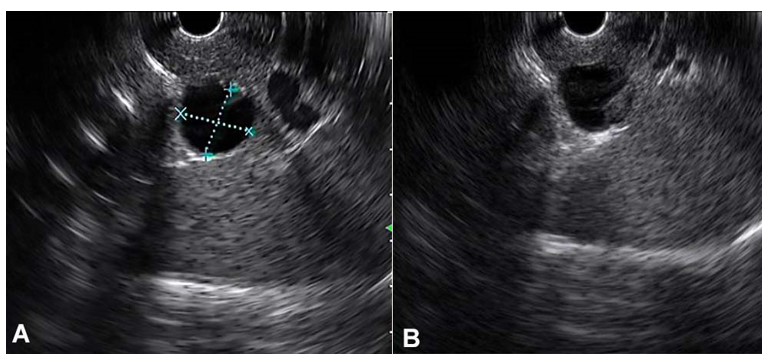

Endoscopic ultrasound with linear echoendoscope was also performed and again revealed a 1.6x1.5cm cystic lesion at the pancreatic tail. There was a thin septum within the cyst and a suspicious 5mm mural nodule (Figure 2). The pancreatic duct was not dilated and apparently lacked communication with the cyst. Fine needle aspiration was performed during the examination and yielded a small amount of light brownish fluid. The cyst fluid showed an amylase level of 879 IU/L (>6,800 IU/L suggests pseudocyst instead of mucinous neoplasms,45 and < 250 IU/L excludes the possibility of a pseudocyst46), and carcinoembryonic antigen (CEA) level of 3582 ng/mL (>800 ng/mL suggests IPMN or MCN46). Cytological examination showed no malignant cells.